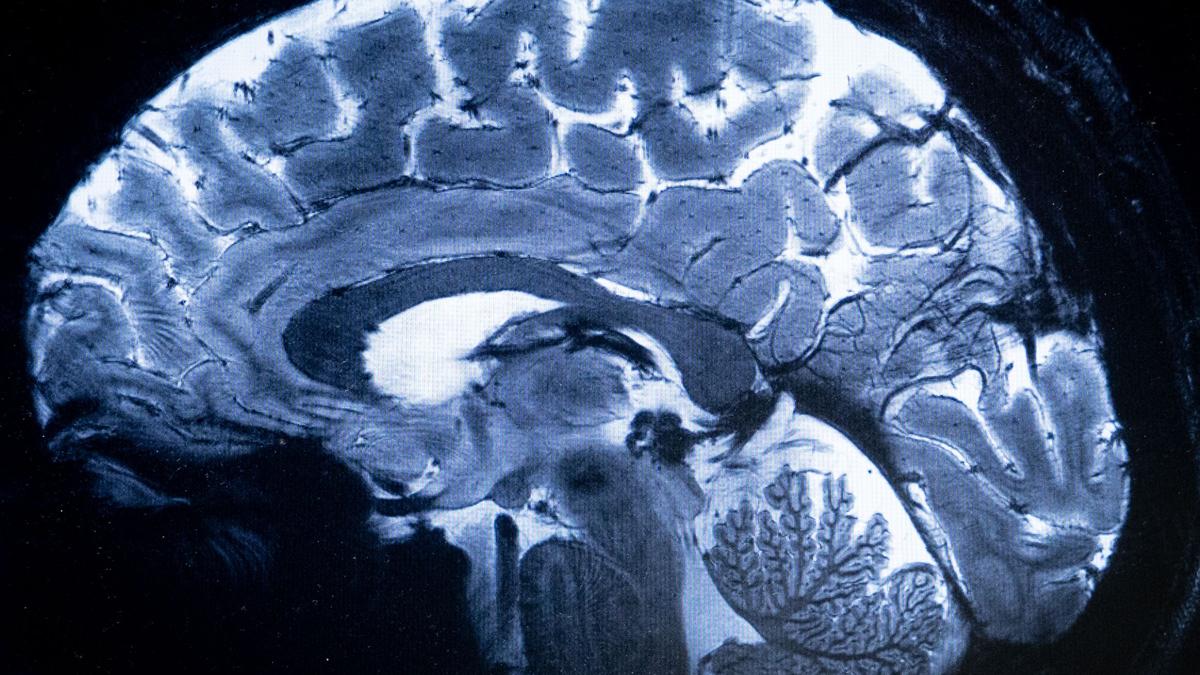

Thiruvananthapuram, 17th Sept: Kerala’s health department has sounded a statewide alert after a sharp rise in Primary Amoebic Meningoencephalitis (PAM), a rare but often fatal brain infection caused by the “brain-eating amoeba” Naegleria fowleri.

A Kerala government advisory describes PAM as a disease that destroys brain tissue, causing severe swelling and rapid death. The amoeba enters through the nasal passages when people swim, dive, or bathe in warm, stagnant freshwater. Drinking contaminated water does not cause infection. Symptoms—headache, fever, nausea, vomiting—appear within nine days of exposure and resemble bacterial meningitis, often delaying diagnosis until it is too late.